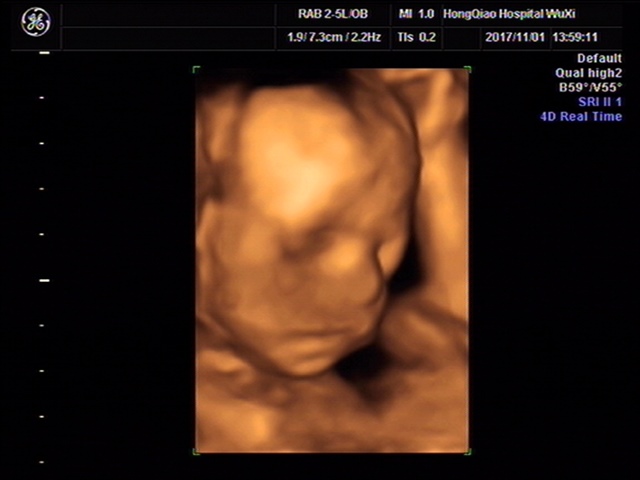

宝妈,这张四维图是孕多少周去照的啊?

美杜莎的凝望[帖主]:23周做的四维拍的